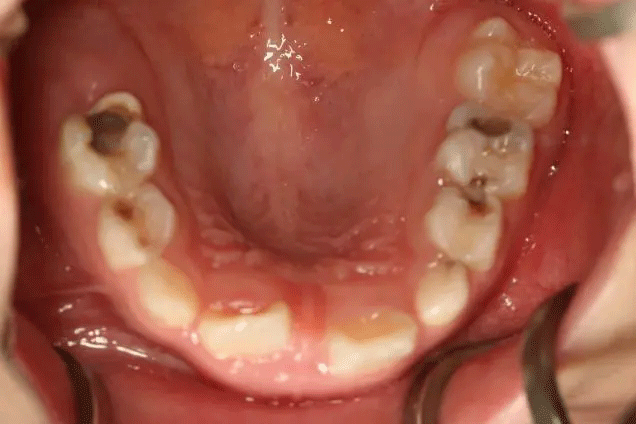

在門診中發(fā)現(xiàn)

來口腔科檢查的孩子

有些牙齒都已經(jīng)爛得很嚴(yán)重了

甚至牙齒幾乎都爛光僅剩下牙根